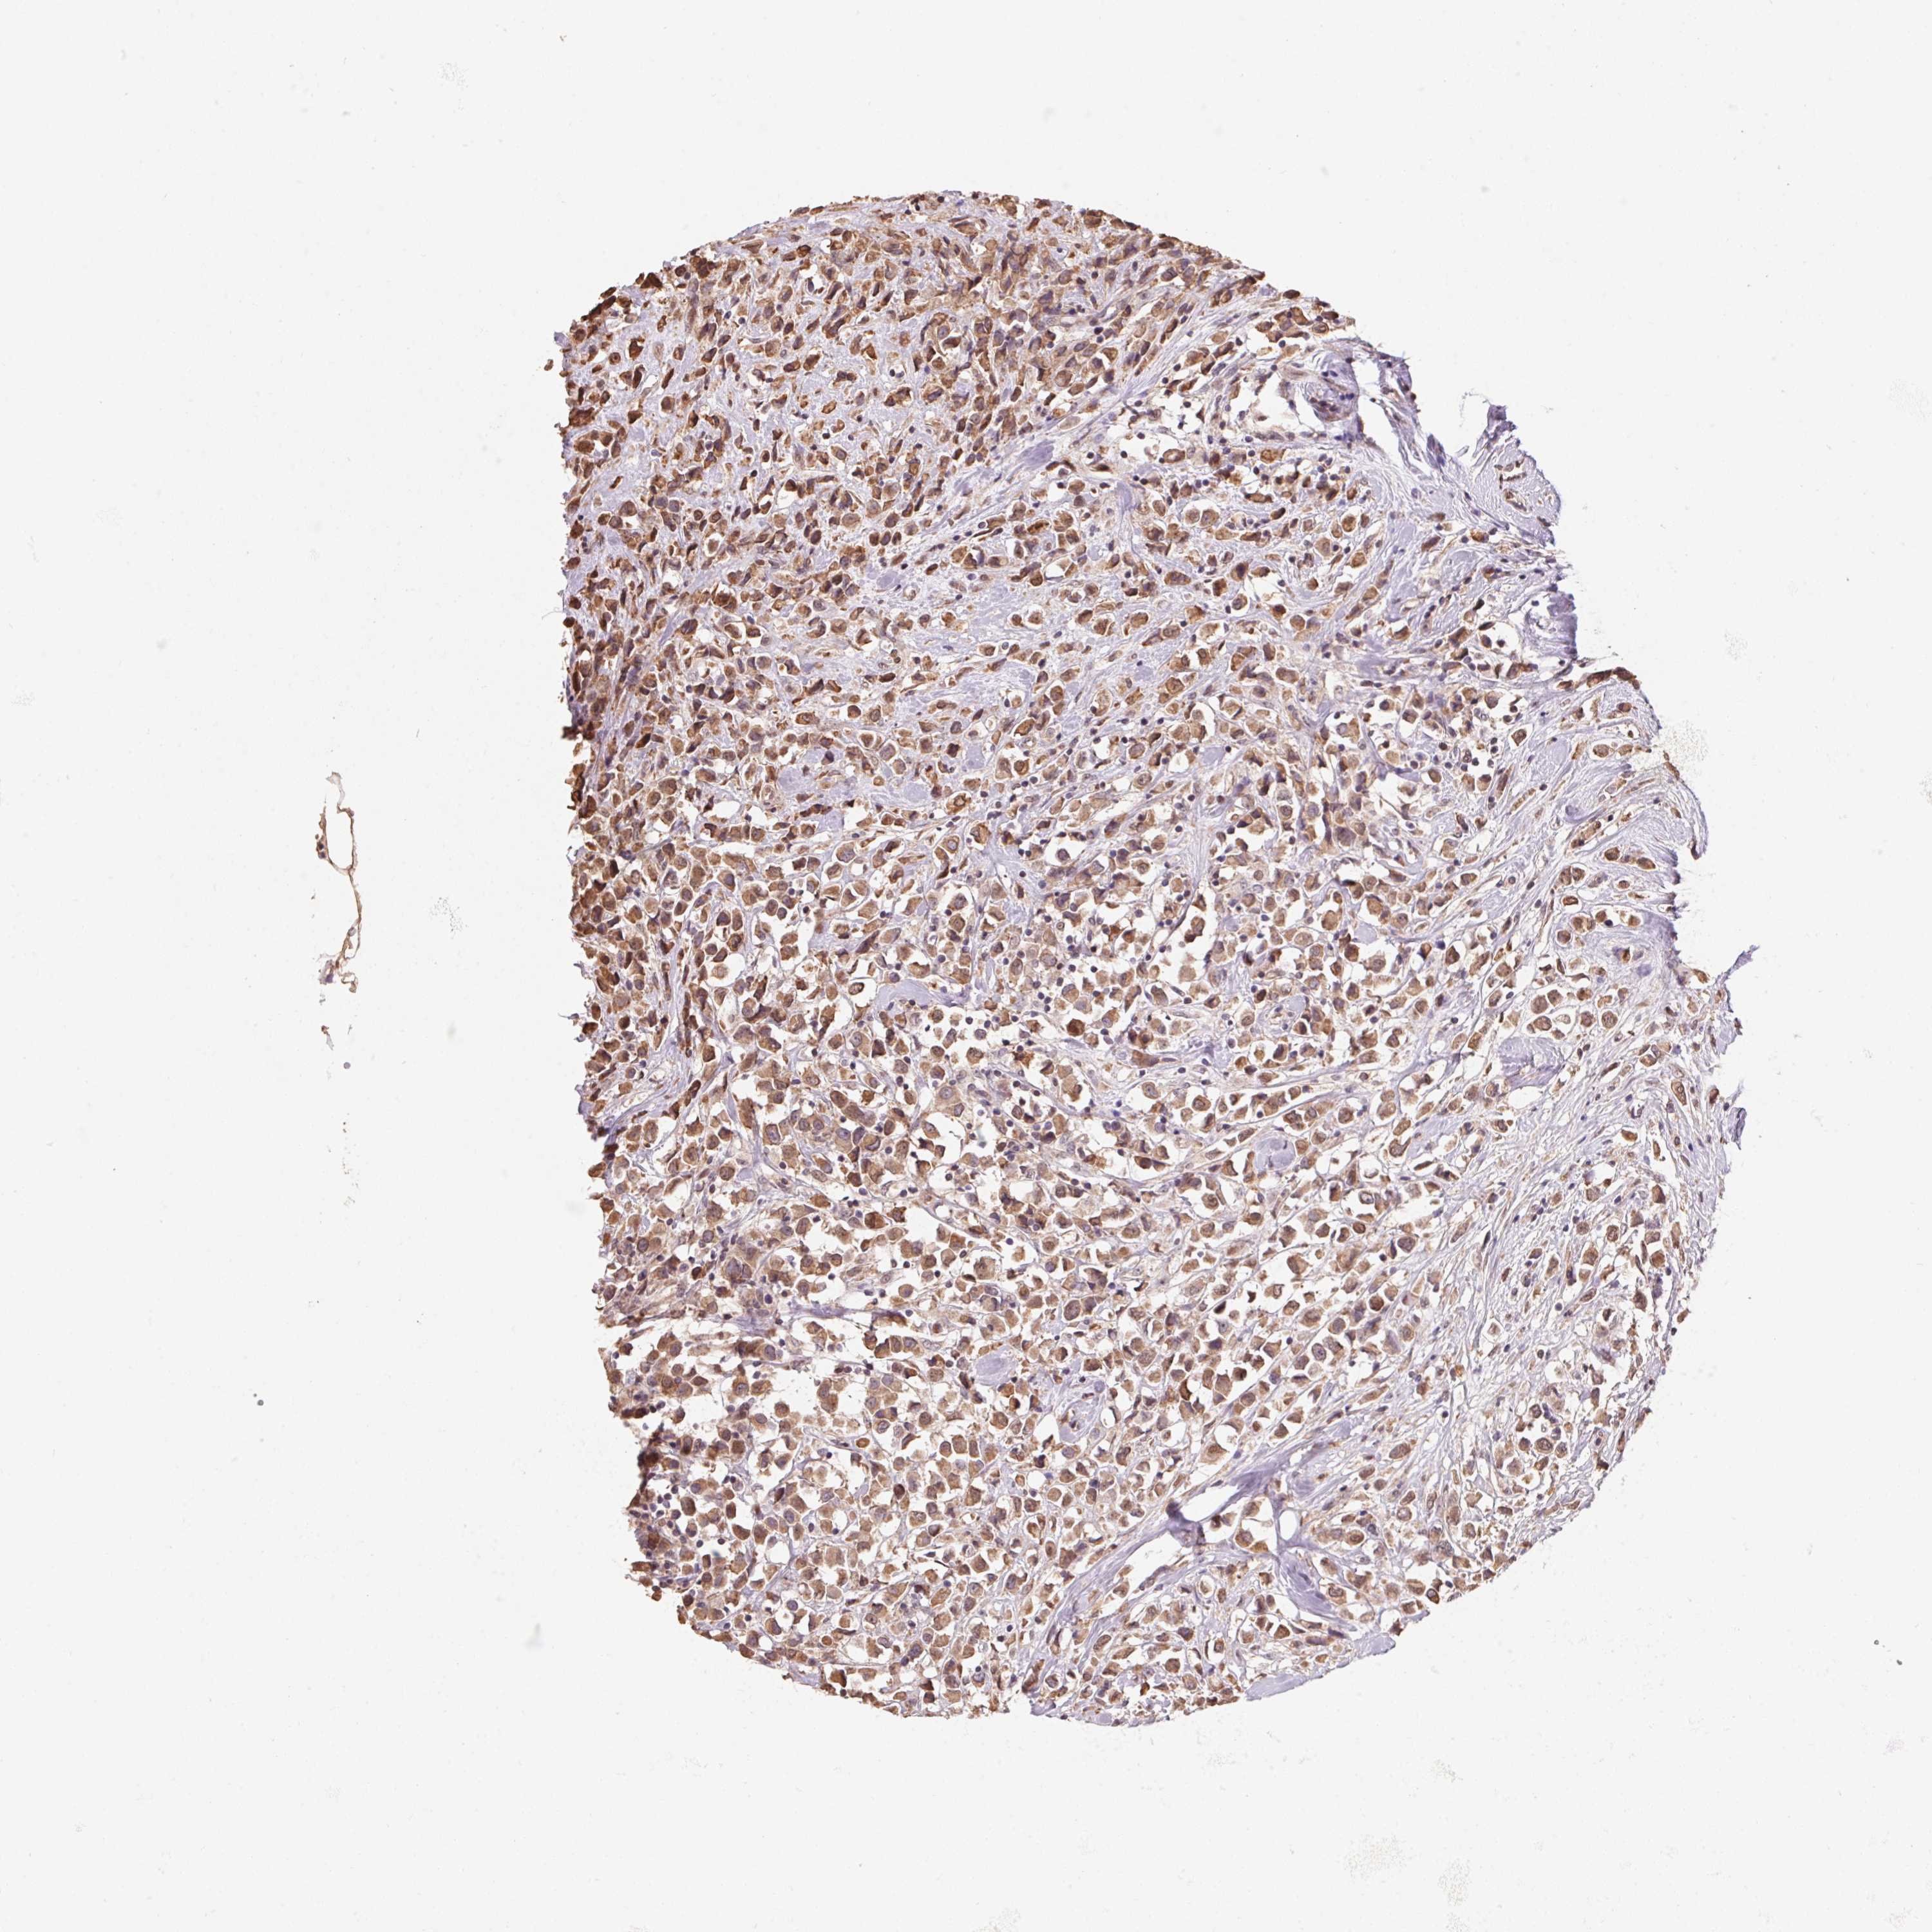

BRCA TCGA BRCA VALIDATION PROTEIN EXPRESSION

ANTIBODIES

AND

VALIDATION